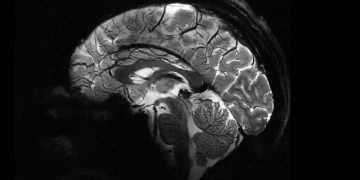

Главным отличием Iseult от них является возможность сканирования мозга в намного более высоком разрешении. Так, всего за 240 секунд он способен сделать снимки человеческого мозга в виде 1-миллиметровых срезов. Обычный МРТ для получения таких результатов потребует 2 часов неподвижного нахождения пациента внутри.

Несколькими годами ранее Iseult испытывался на тыквах, сейчас его протестировали на 20 добровольцах. Полученные изображения раскрывают весь потенциал технологии МРТ и позволяют лучше понять, как работает мозг. При этом, сверхмощный томограф может быть полезен не только ученым, но и медикам. С его помощью можно изучать и диагностировать такие нейродегенеративные недуги, как болезни Паркинсона и Альцгеймера.